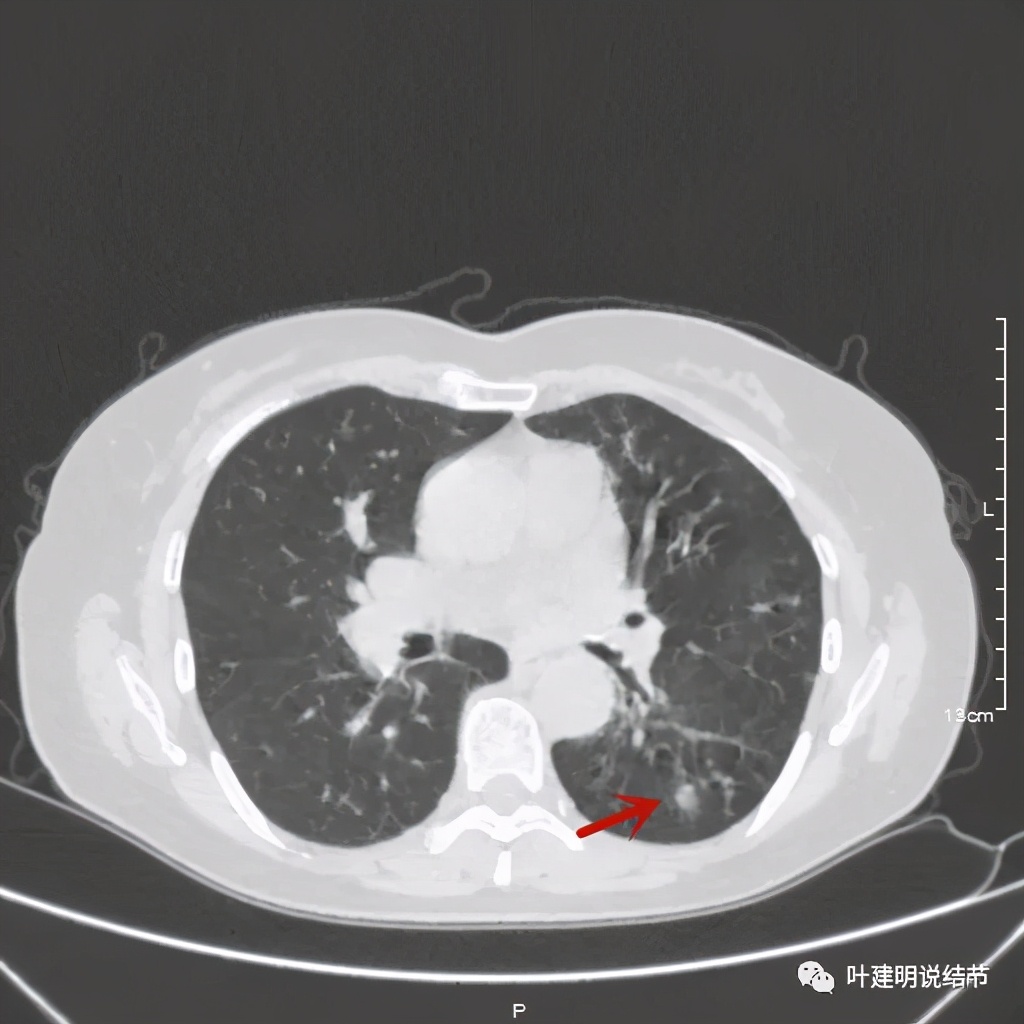

金华的某A,女性,56岁,去年8月份检查发现左肺下叶结节,是实性的,还中间有个空洞,我们说若磨玻璃结节伴空泡或空腔多为恶性范畴的,实性的也是可能性会大一些,但不如磨玻璃确切,因为结核、感染等也会类似的。我们先来看她当时的CT图像:

左下结节与血管关系密切,此层似磨玻璃结节,还夹在小血管之间,其中有血管紧贴病灶,略迂曲

上层见病灶偏实性密度,边缘不光滑